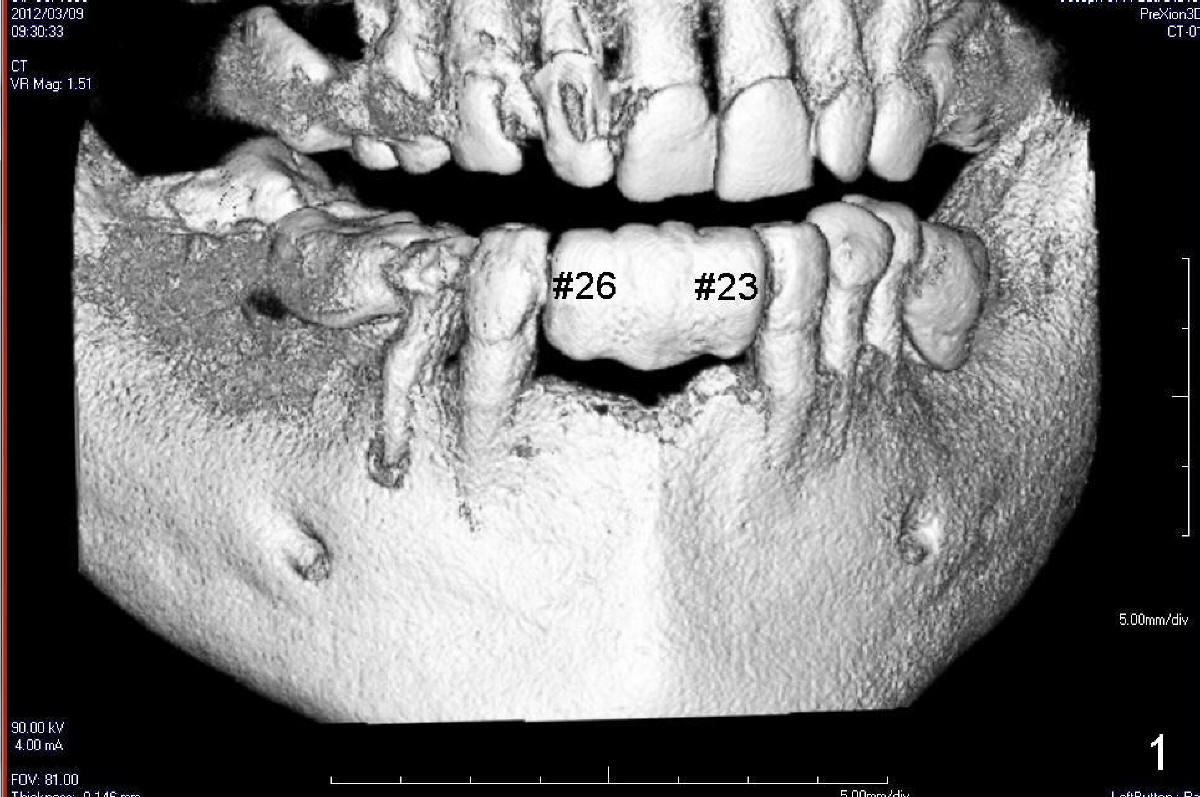

Two of one piece implants (3x17 mm) were placed at the sites of #23 and 26 on February 13, 2013 (Fig.5). The implant at the site of #26 was placed a little too labially with possible coronal labial plate fracture. Immediately fabricated was a provisional FPD, which was replaced by a definitive one three months and a half later (Fig.7).  PA in Fig.6 is taken five months post implantation (I: one-piece implant).